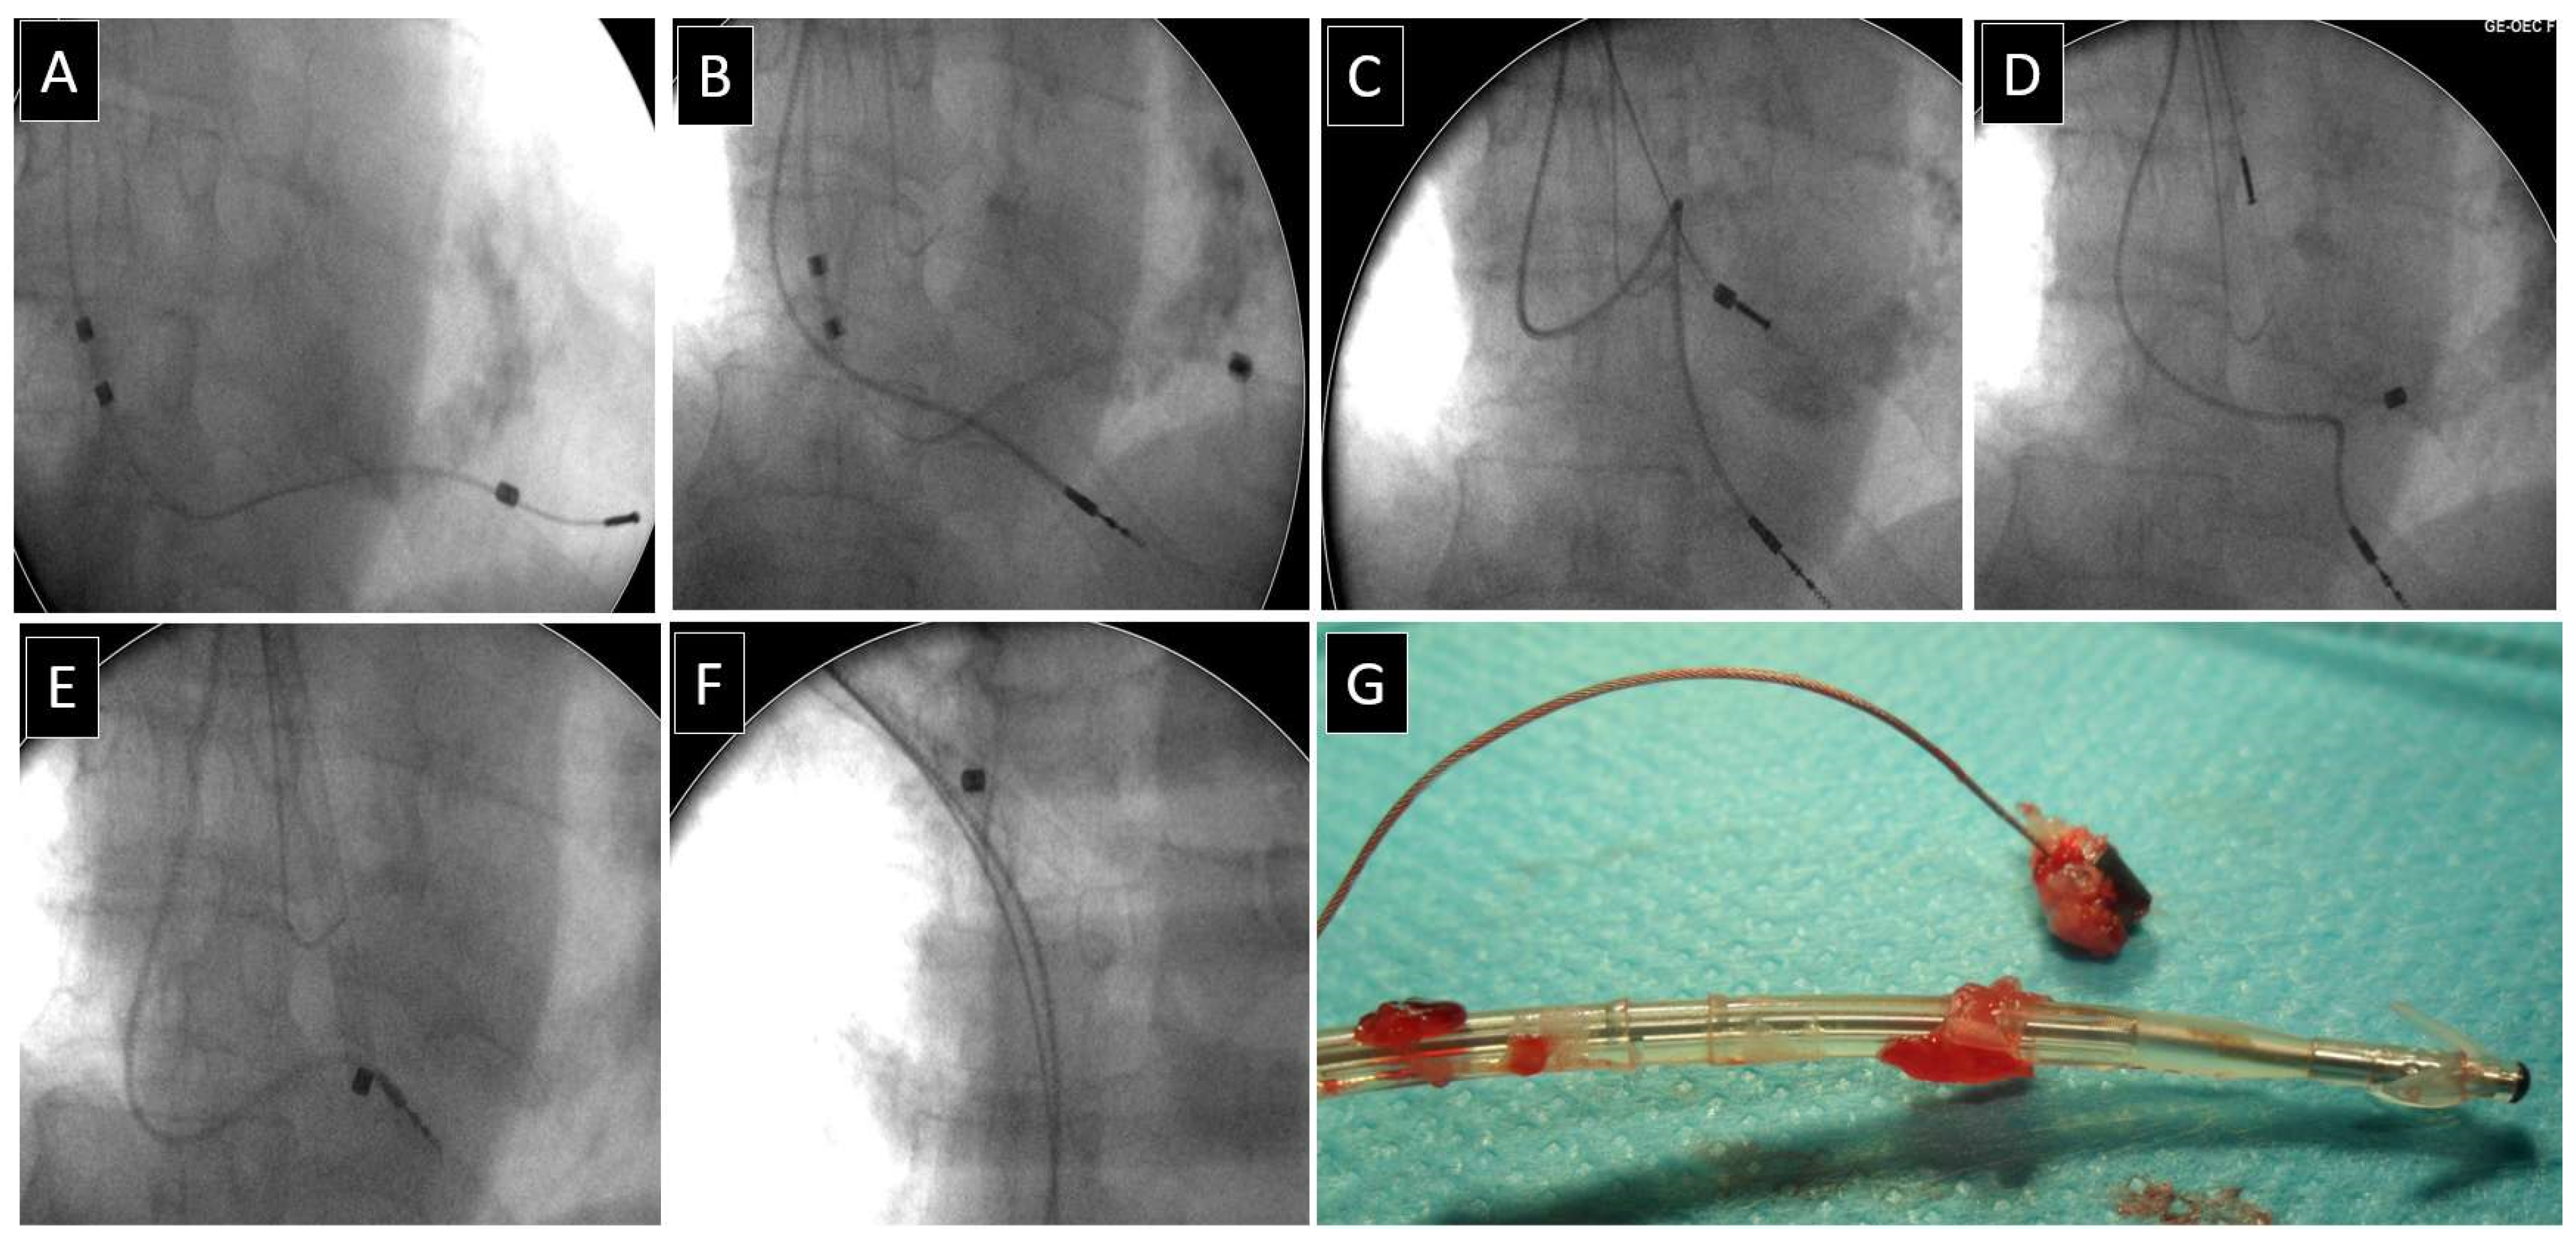

Author Comments on VDD Lead Extraction